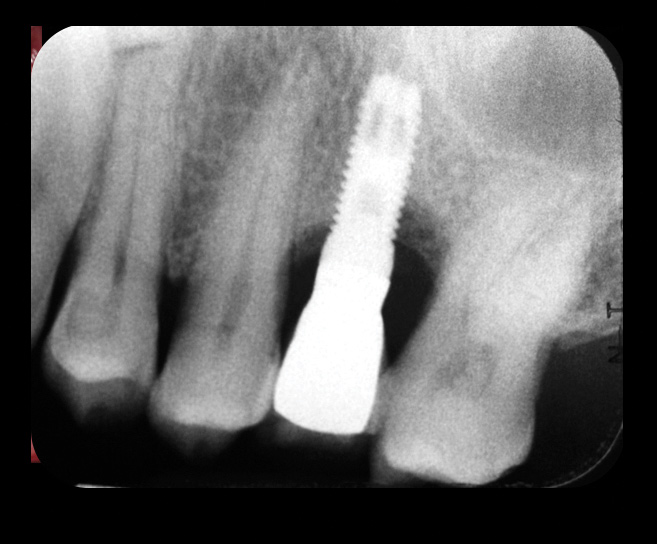

The first step in preventive strategies must be to perform a correct diagnosis of the peri-implant condition by accurately assessing the health of the peri-implant hard and soft tissues through periodontal probing and periapical radiographs at the time of definitive prosthetic installation. These measurements should be considered the baseline diagnosis and, therefore, represent a true starting point for evaluating the changes on the radiographic bone levels and probing pocket depths (PPD) at future recall appointments (Figure 1 and Figure 2).6 Although probing depth measurements of peri-implant tissues do not have the same diagnostic value as probing periodontal tissues, there is evidence that BOP is the most objective sign of peri-implant tissue inflammation; significant deepening of PPD compared with baseline measurements is also a sign of disease that indicates the need to perform a radiographic evaluation (Figure 3 through Figure 5).6,10,11

Fig 13. Radiograph depicting crestal bone loss around mandibular implants.

Figure 13

Fig 14. After removing the prosthesis, presence of peri-implant plaque and calculus.

Figure 14